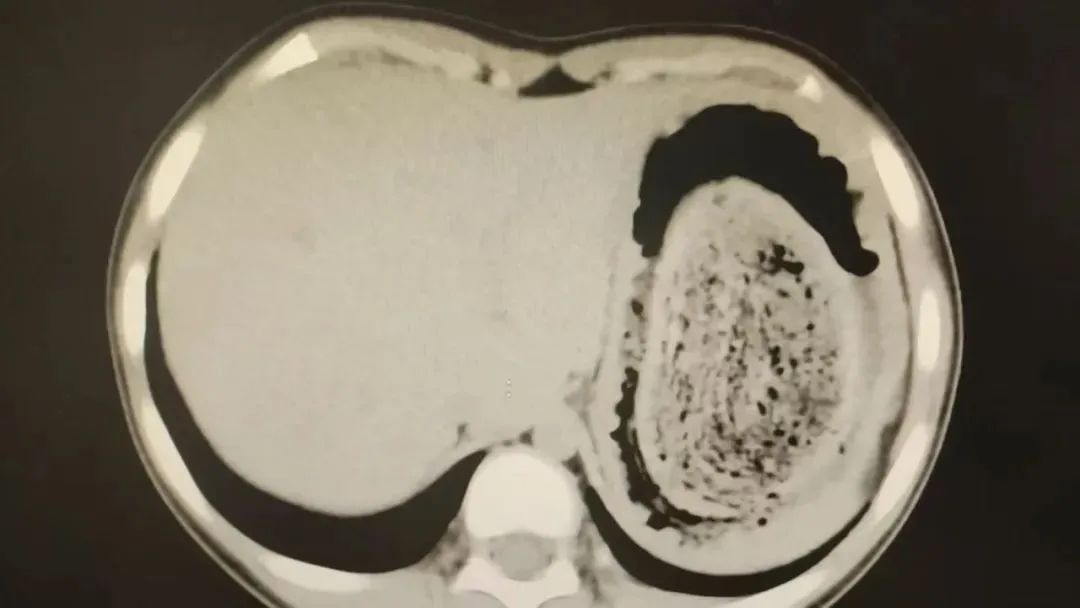

前不久,今年10岁的园园(化名)因持续3天的上腹痛伴呕吐被紧急送医。影像学检查结果显示,她的胃部存在一个巨大的团块状阴影,初步怀疑为异物堵塞。

据主刀医生陈杰介绍,园园的情况较为复杂,胃内的头发团块体积庞大,占据大部分胃腔,严重影响了食物摄入。更棘手的是,部分毛发已进入小肠,引发消化道梗阻。单纯通过胃镜或传统的开放手术难以同时解决两个部位的异物问题,因此选择腹腔镜微创手术,力求在最小创伤下彻底清除异物。

2024年10月,11岁女孩欢欢(化名)因腹痛难耐紧急送到医院,而就在两个月前,欢欢的父母发现她在拔自己的头发,偷偷吃掉。经检查,医生发现她胃腔和肠管里有大块的毛絮状结石,几乎占据整个胃部。最终,一块长38厘米、宽15厘米、厚10厘米的毛发结石被取出。